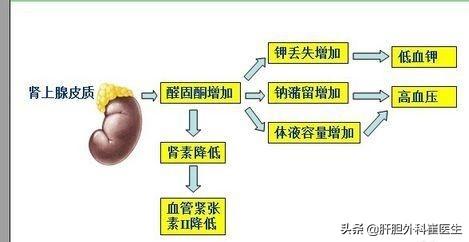

Par ailleurs, les urologues sont parfois confrontés à un groupe de patients souffrant d'une carence en potassium.Anomalies du fonctionnement des glandes surrénalesLa majorité de ces patients présentent des adénomes des glandes surrénales. La plupart de ces patients ont des adénomes des glandes surrénales, dont certains produisent en excès une hormone appelée aldostérone, qui entraîne une excrétion excessive de potassium dans les urines, d'où une grave carence en potassium. Dans ce cas, la carence en potassium est souvent chronique et peut ne pas être ressentie par le patient, mais lorsqu'elle atteint un niveau critique de potassium dans le sang, un accident mortel se produit généralement.

- En ce qui concerne les maladies susceptibles d'entraîner une carence en potassium, il est vraiment possible de multiplier les exemples, car les raisons d'une carence en potassium sont très nombreuses, et la première chose que je dirai est la suivanteAldostéronisme primaireIl s'agit d'un lieu basé sur laHypokaliémie chronique sévère, hypertensionLa principale manifestation de la maladie globale, ce type de patient est souvent l'application de plusieurs types de médicaments antihypertenseurs ne peut pas contrôler la pression artérielle, et généralement apparaîtra la performance du manque soudain d'énergie, si la situation ci-dessus, il est recommandé de consulter un médecin pour vérifier s'il y a un aldostéronisme primaire, la maladie est principalement.Causée par une hyperplasie partielle des surrénales, des tumeurs des surrénales ou même un cancer des surrénales.Il est possible de vérifier les taux d'hormones et la morphologie des glandes surrénales pour établir un diagnostic en clinique, et il est important de détecter et de traiter la maladie à un stade précoce.